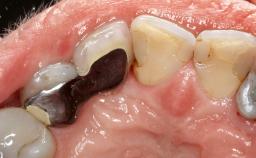

Surgical Management of Peri-Implantitis: Reconstructive Surgical Treatment with Three-Year Follow-up After Treatment

Despite anti-infective surgical treatment, some patients may experience recurrent infection and progressive bone loss requiring additional treatment. Removal of Implant Due to Recurrent Infection describes a conservative approach using an implant retrieval tool without the need for excessive bone removal or use of a trephine.

A 70-year-old female patient was referred by her general dentist to the periodontist for assessment and management of an infection associated with implant 36. The general dentist had noted suppuration on probing during examination.